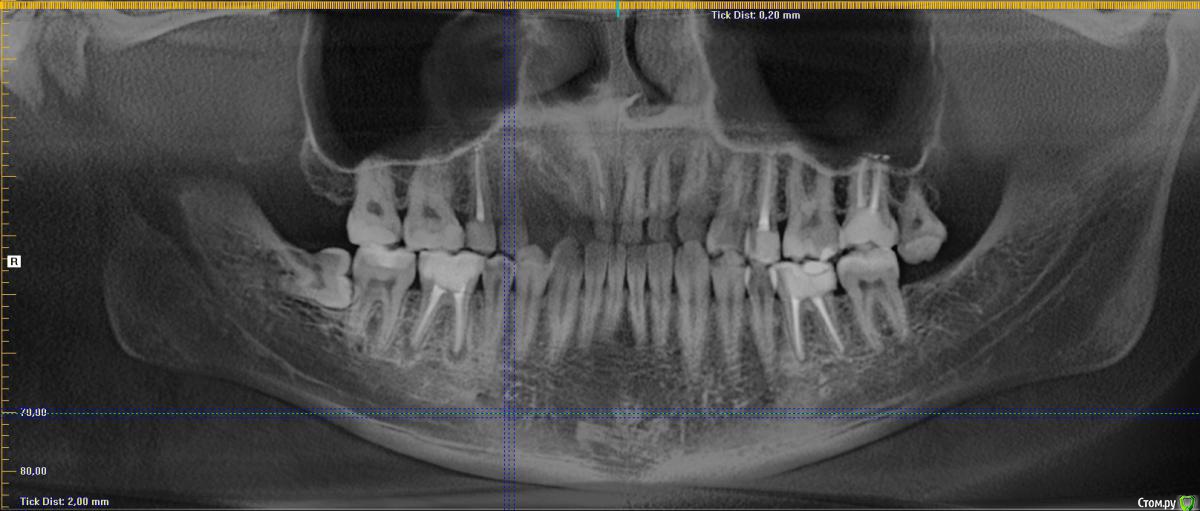

Добрый день! На протяжении нескольких лет обращался на профилактические осмоты - всегда говорили что Ок.

кто говорил, что 8ку удалять. А сходил к хирургу - сказал что все уже вырасло и раз не беспокоит - можно не трогать. Показаний нет.

В сейчас, опять сделали снимок и говорят, что на соседнем зубе кариес, причем значительный - и скорее всего нужно удалять нервы на 7ке, после удаления 8ки. Обращался по страховке.

Снимок не дали, но есть 2х летней давности. Есть ли здесь кариес или это просто тень от 8ки?

удаление 48,28

15,25,27,36 протезирование коронками

46 - повторное лечение и протезирование

А на 47 видно следы кариеса?

Есть какая-то зона деминерализации. Лучше свежий снимок сделать.